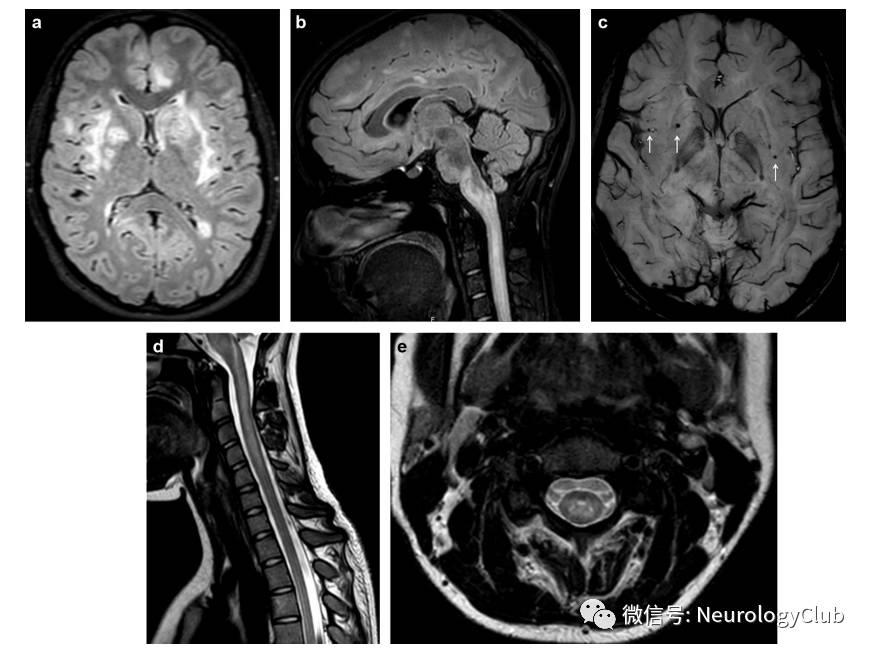

案例59岁女孩,头痛、呕吐伴视物模糊15天。既往两次周围性面瘫病史。神经科查体未见明显阳性体征。血压225/110mmHg。实验室检查:血红蛋白8.8g/dL,肌酐1.77mg/dL,尿素氮38mg/dL。腰穿压力正常,脑脊液蛋白轻度升高(57mg/dL),IgG合成指数0.9,有核细胞10/10^6,红细胞70/10^6。寡克隆带阴性。TORCH、病毒性检测阴性。抗核抗体阴性。血NMO抗体阴性。B超示双侧肾脏萎缩。患者接受短暂的激素治疗。1周后症状缓解,10天后复查MRI病灶完全吸收。

(图15:颅脑MRI可见延髓和颈髓异常信号